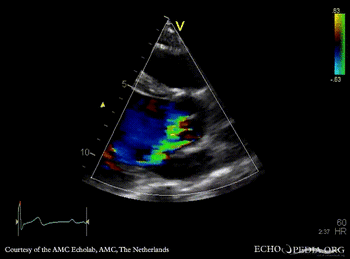

E00233.gif E00234.gif

A4CH: left ventricle dilatation A3CH: Color Doppler, severe aortic regurgitation